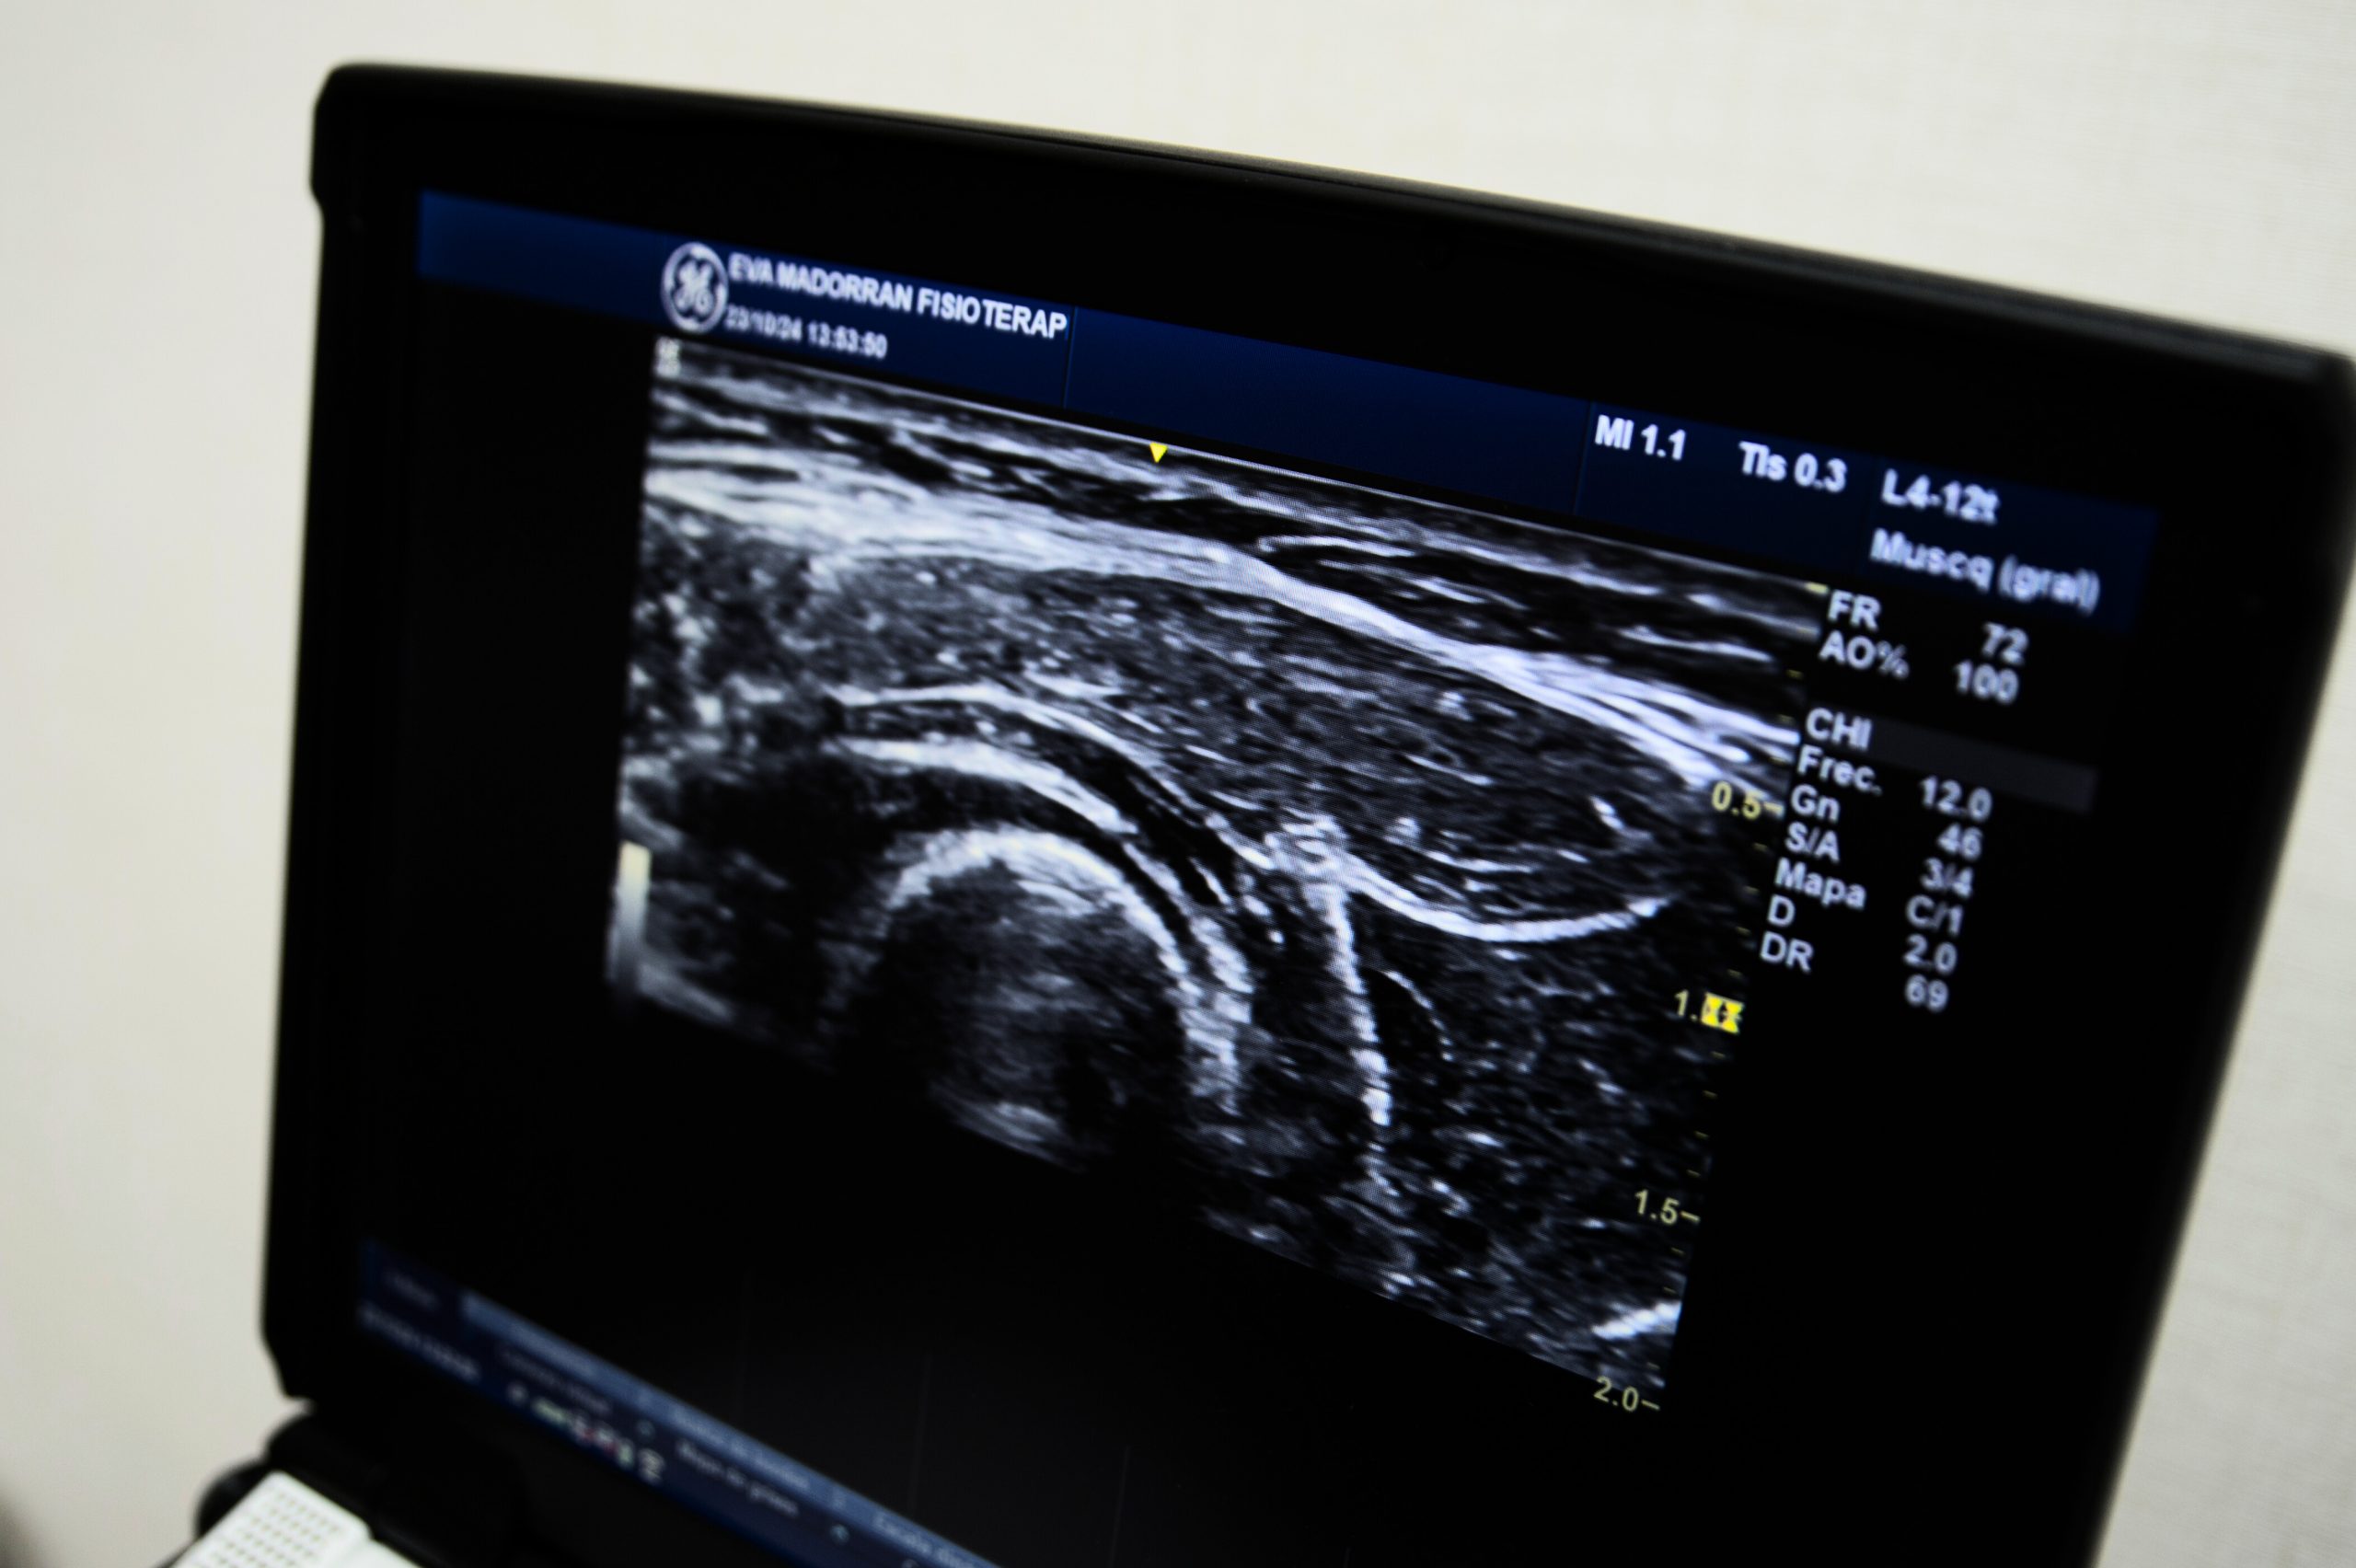

La ecografía musculoesquelética es una técnica de imagen no invasiva que utiliza ultrasonido para visualizar en tiempo real las estructuras del sistema músculoesquelético, como músculos, tendones, ligamentos, articulaciones, nervios…

Esta herramienta permite a los fisioterapeutas realizar una evaluación más exhaustiva y dinámica de las lesiones, identificando alteraciones que podrían no ser visibles a través de métodos tradicionales.

• Tratamientos ecoguiados: Aumentamos la precisión de técnicas como punción seca o electrólisis percutánea intratisular (EPI), garantizando un enfoque seguro y eficaz.